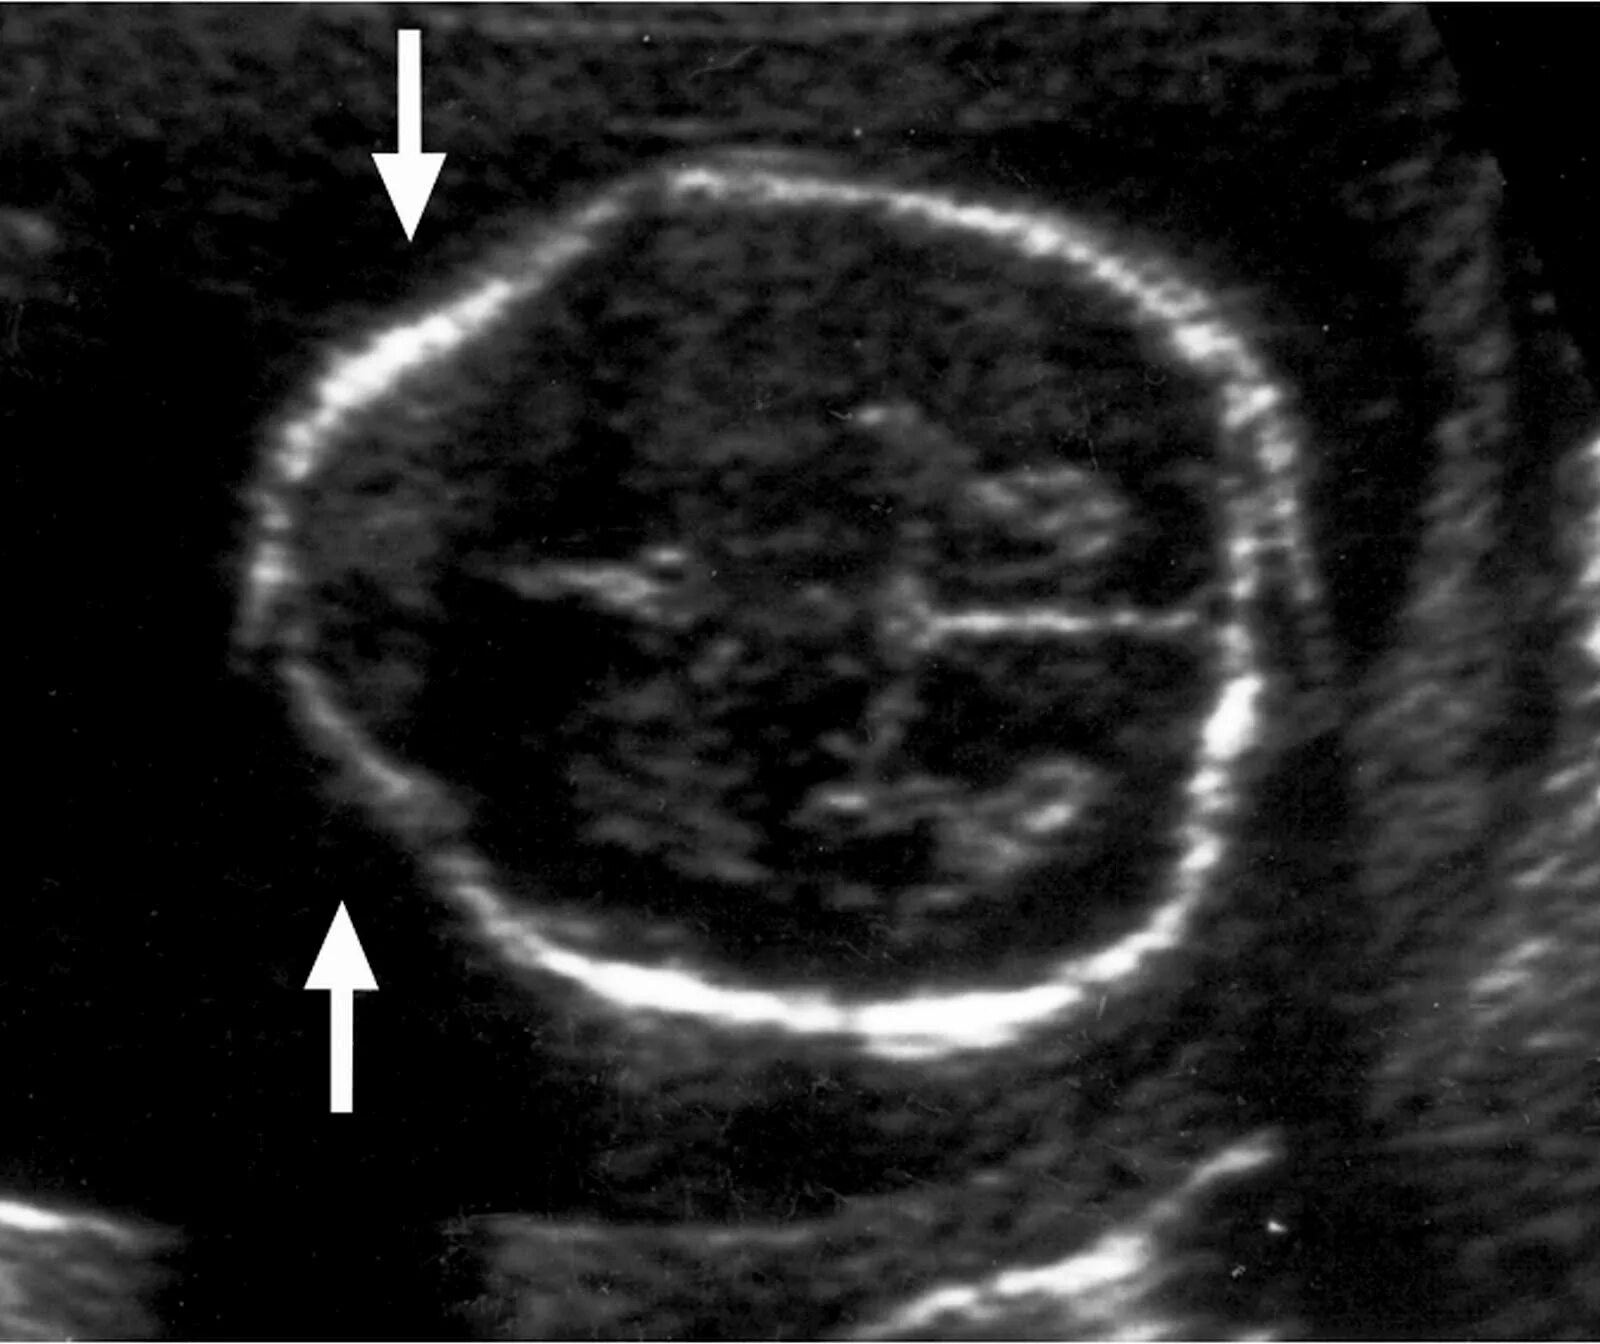

Узи аномалий